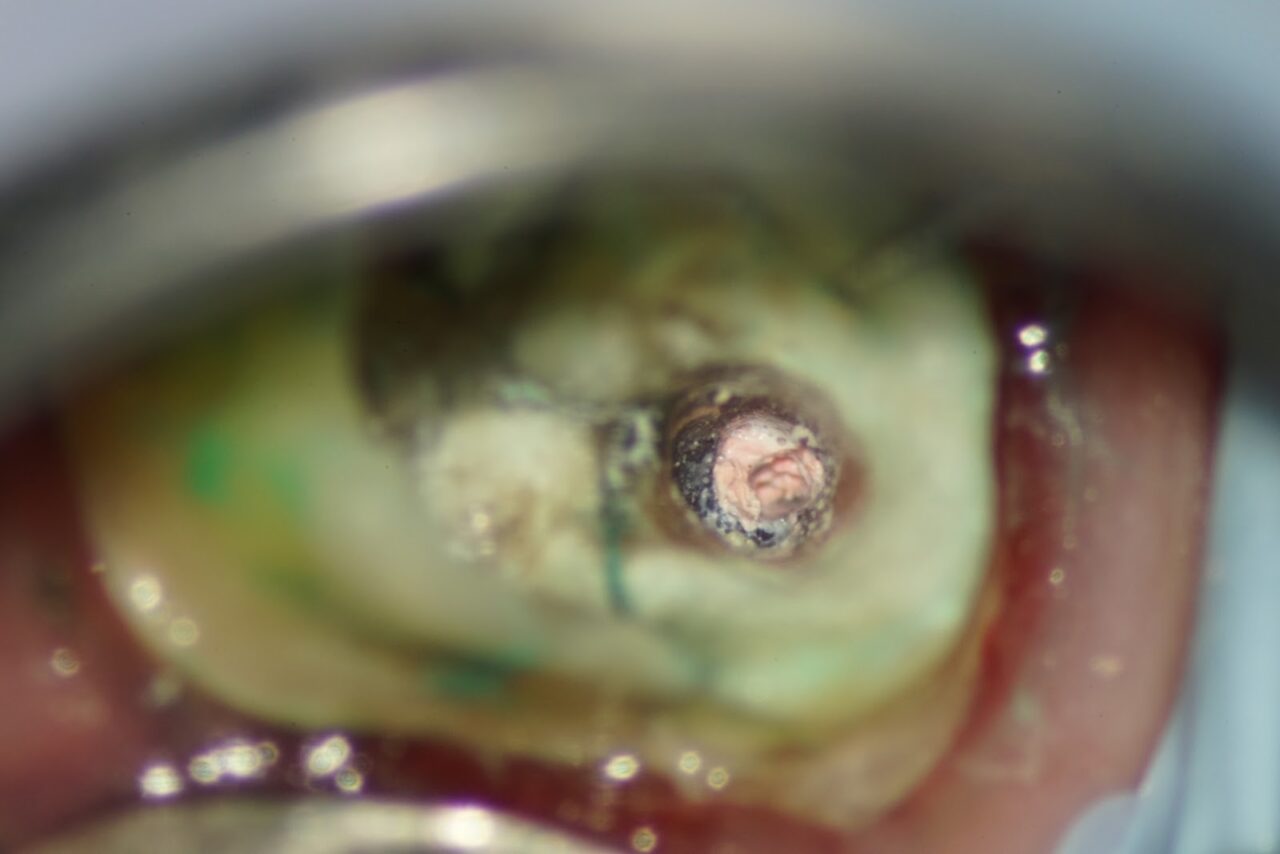

麻酔をした後にラバーダム防湿を行い、ジルコニアと思われるクラウンを外します。

クラウンを外すとレジンコアが入っており、少し削ると感染して変色した破折線が確認されました。

根管内の古い充填物を除去していくと近遠心に繋がる破折線がより明確に成ってきました。

一般的な治療、大学病院やアメリカ帰りの歯科医師では破折線が確認された時点で抜歯の診断基準を満たしており、抜歯と診断され、この時点で治療終了になります。

吉松歯科医院では、破折歯の治療を15年以上前から続けており、15年を超える症例もあります。

感染部が緑色に染まるう蝕検知液で、感染部の除去を徹底して行います。

以前の根管内の充填物が除去する事が出来たので、破折線の感染除去を行います。

破折線を可能な限り細い器具で感染部を除去して行きます。

破折線の処理がほとんど終わった状態です、少し前の写真と比べるとキレイに成っている事が確認できます。